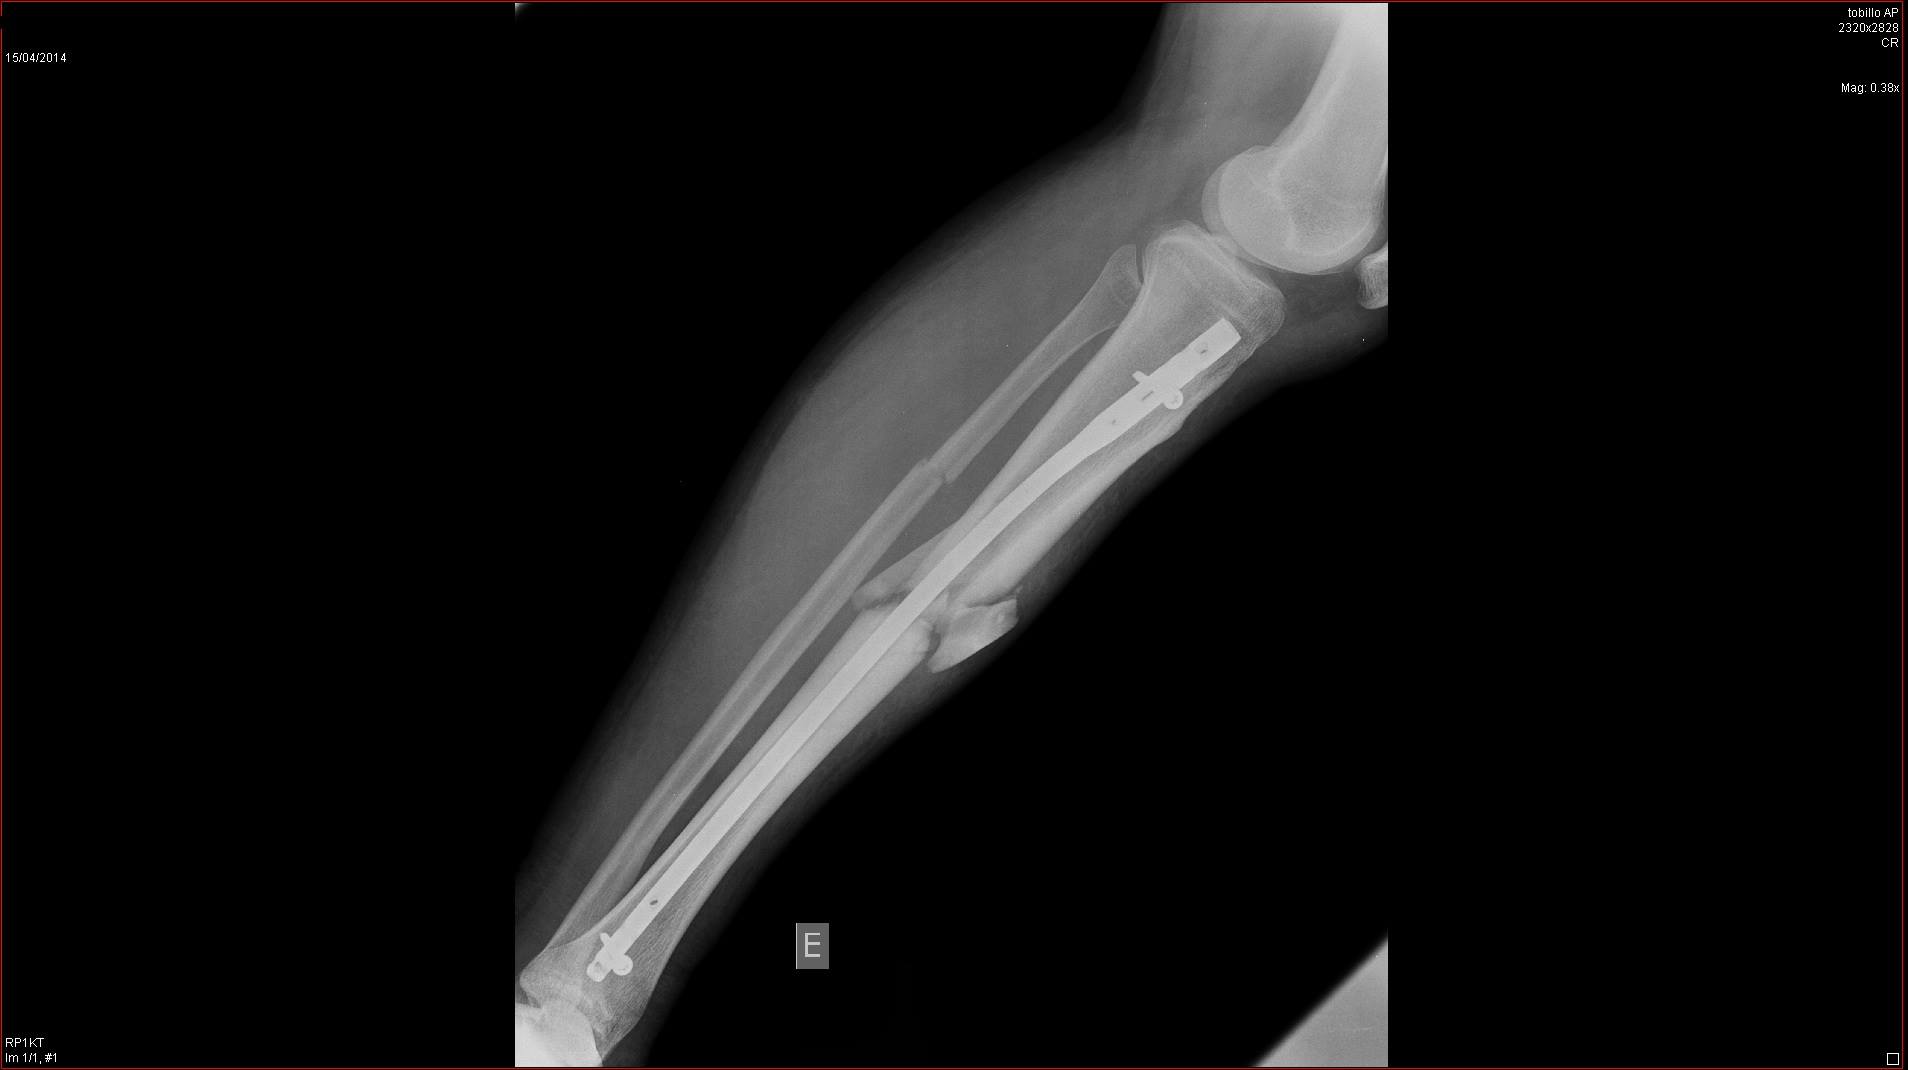

Ahora mismo es lo unico que puedo hacer, recordar los buenos momento, tengo la tibia y peroné rodas y estilladas desde hace 4 meses, más lo que me falta para volver a caminar, así que toca esperar y tener paciencia :(

Yo llevo 4 meses en el dique seco, me quedo asi la pata despues de ser atropellado en un paso de peatones por una moto que adelanto a un coche que me estaba cediendo el paso (Que aun tiene más delito!)

Despues de 4 meses aun lo tengo así

Pero como el mono es tan fuerte, ya empiezo a darle a pata coja! Ya que ni tengo ni la tibia ni peroné pegados, apenas puedo mantenerme de pie con esta pierna :(

Yo este año me quedado sin hacer el Campeonato Challenger Master30 de Catalunya, ni el campeonato de larga distancia, ni las classicas de verano, y lo que queria hacer con más ilusión de todo, el campeonato de Catalunya de CicloCross :( Finalmente este lunes me volvieron a operar despues de los contratiempos de la semana pasada, me recuperación aun sera más lenta de lo esperado :(